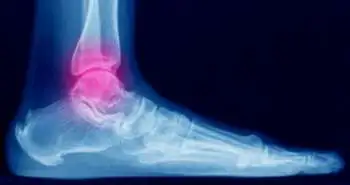

Syndesmotic injuries at the ankle joint are injuries to the ligaments that connect the tibia and fibula. They are the most severe ligament injuries to the ankle, and occur either in isolation or at the same time as an ankle fracture. External rotation and/or hyperdorsiflexion are the most common mechanisms causing syndesmotic injuries. These injuries can occur during activities like sports or dancing, and any other fall. Patients with syndesmotic injuries like acute ankle sprains experience acute ankle instability, pain & functional problems.